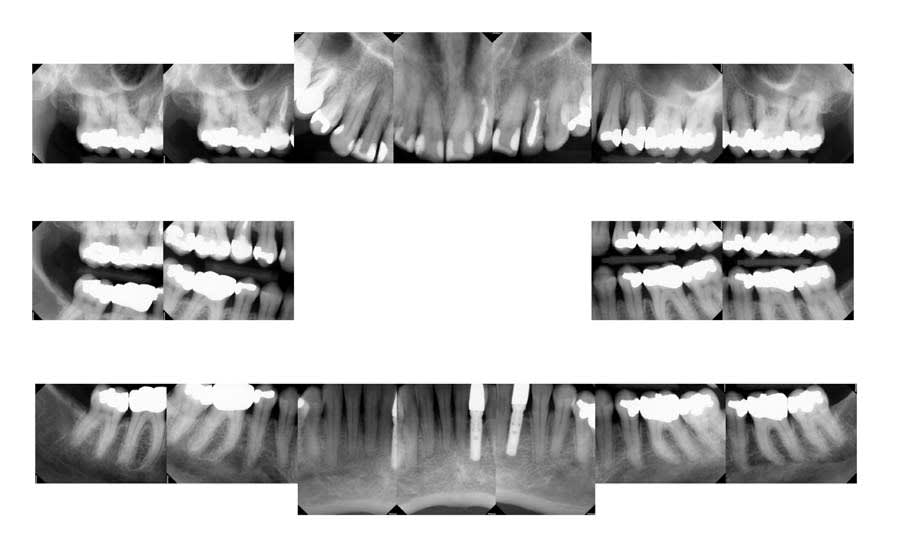

Periodontal: The patient had maintained consistent 6-month dental visits for 30 years. She presented with generalized mild recession (1 mm to 2 mm on multiple teeth), a stable free gingival graft from 20 years prior, and prescription fluoride toothpaste use. Radiographs showed generalized interproximal bone levels of 2 mm to 3 mm from the cementoenamel junction (CEJ) and probing depths of 1 mm to 3 mm, except for localized 4 mm pockets on teeth Nos. 14 and 19, mesial and distal surfaces, respectively. No mobility was noted, and there was no bleeding on probing except on the distal surface of tooth No. 3. Statin use may have reduced inflammation, supporting periodontal stability. She was classified as American Academy of Periodontology (AAP) stage II, grade A (Figure 3).2

Biomechanical: No active caries or xerostomia was noted, but the fractured amalgam on tooth No. 30 prompted urgent treatment. Large restorations on teeth Nos. 2, 3, 12 through 15, 18 through 20, and 31, along with large Class III composites on teeth Nos. 6 through 9, indicated structural compromises. Root canal treatment on teeth Nos. 4 and 10 (apicoectomy and post-and-core [FlexiPost®, Essential Dental Systems, edsdental.com]) and marginal fractures on teeth Nos. 5 and 12 put these teeth at even further risk. Despite the lack of symptoms, future pulpal pathology was a risk for many of the patient’s structurally compromised teeth (Figure 4 and Figure 5).

Functional: Moderate anterior attrition (1 mm to 1.5 mm) was noted, particularly on teeth Nos. 6 through 9 and 24 through 27, with no significant posterior wear or abfraction lesions. The patient reported slow progression of attrition on her front teeth that had stabilized over the past 5 years, corroborated by a historical photograph. Temporomandibular joint (TMJ) evaluation revealed a 40 mm maximum opening with slight right deviation, asymmetrical lateral movements (8 mm right and 11 mm left), and no pain or joint sounds. She had facial asymmetry as her chin point was 2 mm right of center. CBCT imaging showed a non-reducing anteriorly displaced disc in the right TMJ with osteophyte formation and reduced cortical bone, contrasting a normal left TMJ (Figure 6). Occlusal dysfunction was suspected due to her aberrant chewing pattern, which resulted in unilateral attrition and clenching. Her initial deprogramming identified the first contact on tooth No. 2 with a slide into maximum intercuspation, supporting an occlusal dysfunction diagnosis.